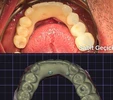

Fotoğraflar